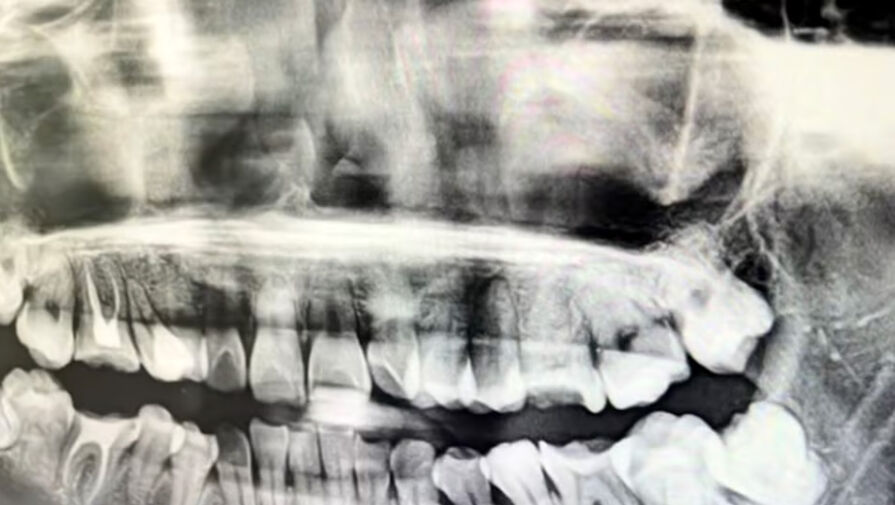

Истончение кости вокруг зубного импланта чаще всего происходит из-за естественного снижения нагрузки на костную ткань, инфекций и неправильного выбора изделия. Курение и сахарный диабет дополнительно повышают риск. Об этом «Газете.Ru» рассказал кандидат медицинских наук, врач-стоматолог-имплантолог Игорь Кузьмин.

Кость — это живой орган, который постоянно перестраивается: старые участки разрушаются, новые строятся. Появление импланта из титана вносит изменения в этот баланс.

«Одна из причин — биомеханика. Имплант не имеет естественной связки зуба, которая амортизирует нагрузку. Жесткий титановый корень забирает на себя давление при жевании, а кость вокруг получает меньше стимулов, что может приводить к ее истончению», – пояснил специалист.

Стоматолог добавил, что даже конструктивные особенности импланта влияют на здоровье кости. Микрозазоры между ним и абатментом (опорой) могут стать «входом» для бактерий, поэтому современные системы стараются сделать соединение герметичным. Быстрая и надежная остеоинтеграция — срастание кости с имплантатом — также снижает риск истончения.